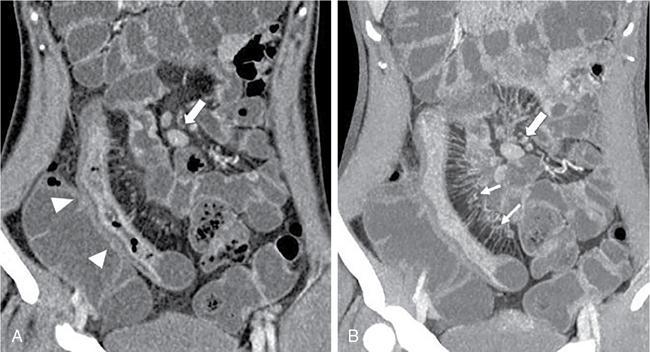

Kavita Saggar, Archana Ahluwalia, Devinder Pal Singh Dhanota, Geetika Khanna, Chander Gupta Inflammatory bowel disease (IBD) represents chronic idiopathic inflammation of the gastrointestinal [GI] tract. The common subtypes are Crohn’s disease, ulcerative colitis (UC) and indeterminate colitis (Fig. 7.11.1). Approximately 20%–25% of patients present in childhood or adolescence. Of these, nearly two-thirds of cases are caused by Crohn’s disease with an incidence of 4.56 per 1000,000 children (Fig. 7.11.2). IBD can affect any portion of the GI tract; however, children have a much higher incidence of small bowel and colonic involvement (Table 7.11.1). Currently, there is no single diagnostic test for the evaluation of IBD. Diagnosis is based on a combination of history, physical examination, serum inflammatory markers, endoscopy, histopathology and imaging. A host of imaging modalities is available for the evaluation of IBD in children. Traditionally, barium fluoroscopic studies, namely small bowel follow-through or small bowel enteroclysis (SBE) were used. However, barium studies depict only the mucosal abnormalities and do not evaluate the extraluminal extent of disease. Ultrasonography (US) is increasingly being used in the workup of patients with IBD. Small intestine contrast ultrasound (SICUS) and contrast-enhanced ultrasound (CEUS) are used for evaluation of IBD. CEUS requires intravenous administration of microbubble contrast such as Sonovue, and SICUS requires small bowel adequate luminal distension with ingestion of an iso-osmolar contrast agent such as polyethylene glycol. A recent meta-analysis of 33 studies showed that CEUS had better accuracy than US, CT and MR for the detection of inflammation and differentiation of fibrotic and inflammatory strictures. However, the extent of the disease was better evaluated by CT and MR. Currently, computed tomography enterography (CTE) and magnetic resonance enterography (MRE) have emerged as the most effective tools for imaging small bowel in patients with IBD. CTE and MRE can accurately depict the spectrum of imaging findings related to severity, extent and complications of IBD and thereby help in guiding management and assess the response to treatment. MRE is an attractive imaging modality due to lack of ionizing radiation, inherent multiplanar capability and excellent soft tissue contrast resolution. In addition, dynamic/cine imaging allows assessment of peristalsis and accurate identification of the diseased segment. The major disadvantage of MRE is high cost, lower spatial and temporal resolution and long examination time. Crohn’s disease is a transmural granulomatous disease that can affect any part of the GI tract from the oral cavity to anus, often involving multiple discontinuous segments of bowel. Patients have a genetic predilection to develop an abnormal immunologic response to environmental factors including food and gut flora, leading to a chronic inflammatory response. Small bowel is the major site of involvement. Terminal ileum is the most common location which is involved in approximately one-third patients. The colon is affected in 50% patients. In 15%–20% cases, there may be isolated involvement of the colon without affecting the small bowel. The clinical importance of small bowel Crohn’s disease is the impact that a diffuse small bowel disease is expected to have on child’s growth and development. Thus, objective evaluation of small bowel is essential in differentiating from other enteropathies and in directing the management of patients with IBD. Two methods used for imaging small bowel with barium using fluoroscopy are standard small bowel follow through (SBFT) and SBE. Small bowel evaluation with barium has long been considered the most common, noninvasive, inexpensive and easily accessible radiological method, but it has been replaced by cross-sectional imaging. In the current scenario, the only indication of barium studies is when CTE or MRE cannot be done because of nonavailability or are not feasible. Ultrasound is being increasingly used to assess the activity of Crohn’s disease, especially in paediatric patients. Greyscale ultrasound allows morphologic assessment of bowel wall and mesentery. Normal small bowel loops are easily compressible with the transducer and the wall thickness is <2 mm. The bowel loops show regular peristalsis and are mobile. Colour Doppler shows minimal intramural or perienteric vascularity. The salient sonographic features of Crohn’s disease are: There is marked concentric or eccentric bowel wall thickening [>2.5–3 mm]. The mural echogenicity depends upon the degree of inflammation and fibrosis. In the acute phase, mural stratification is maintained (Fig. 7.11.3A and B). In patients with long-standing disease, a target or pseudo-kidney appearance may be seen. In long-standing burnt-out disease, there is submucosal fat deposition. The actively inflamed bowel segments show increased vascularity on Doppler ultrasound (Fig. 7.11.4A and B). CEUS with microbubbles can objectively assess the disease activity. A stricture is seen as a segment of bowel wall thickening with apposition of the luminal surfaces. There is persistent luminal narrowing with variable degree of upstream dilatation and hyperperistalsis. Doppler imaging reveals hyperemia in strictures with an active inflammatory component. Fibrotic strictures do not demonstrate increased blood flow. A major advantage of ultrasound is real-time imaging which allows the evaluation of bowel peristalsis. The diseased segments of the bowel (inflamed or fibrotic) show reduced peristalsis and often appear fixed in position. Mesenteric inflammation is commonly seen in active Crohn’s disease. Sonography reveals thickening of mesentery with heterogeneous echogenicity due to oedema. Doppler ultrasound shows increased vascularity due to engorgement of vasa recta. Fibrofatty proliferation of mesentery seen in chronic disease appears as abnormally thickened echogenic fat that displaces the bowel loops. Reactive mesenteric lymph nodes (up to 1.5 cm) can be seen in the active inflammatory phase of Crohn’s disease. These appear as hypoechoic round or oval structures with preserved fatty hilum. Sinus tracts and fistula often arise from or just proximal to a strictured segment and appear as linear areas of altered hypoechogenicity extending from serosal surface of gut. There may be tethering and/or angulation of the affected bowel segment. Abscesses are discrete well-defined fluid collections with internal debris, septation or nondependent echogenic gas. Colour Doppler reveals peripheral hyperemia with absent blood flow centrally. Ultrasound may be falsely negative if an abscess contains a large amount of air and can be mistaken for an air-filled bowel loop. Both CTE and MRE identify the transmural, extramural and mesenteric manifestations of small bowel Crohn’s disease. The imaging findings can be categorized as: Asymmetric long segment (>3 cm) bowel wall thickening is a consistent feature of Crohn’s disease. The mesenteric border is usually more severely affected. It is imperative that the bowel should be distended when assessing bowel wall thickening. Thickening may be mild (3–4 mm), moderate (5–10 mm) or severe (>10 mm) (Fig. 7.11.5A and B). This is the most consistent finding in the active inflammatory stage, defined as increased signal intensity or attenuation on contrast-enhanced scans in a noncontracted segment of bowel in comparison with adjacent small bowel segments. Hyperenhancement may be stratified into bilaminar and trilaminar patterns. In the bilaminar pattern, there is hyperenhancement of only the inner wall (often referred to as mucosal hyperenhancement), and in the trilaminar pattern, there is inner and outer wall hyperenhancement, with the submucosal oedema giving a halo effect. Hyperenhancement may also be homogeneously transmural or patchy. A potential pitfall in contrast enhancement is that normal jejunal loops enhance more than ileal loops and collapsed bowel segments can show apparent hyperenhancement (Figs. 7.11.6A,B and 7.11.7A–C). These are defined as multifocal (>3) segmental areas of involvement with normal intervening gut loops. This is an important feature that differentiates Crohn’s disease from UC when colon is predominantly involved (Figs. 7.11.5A,B and 7.11.7A–C). This is identified as an increased signal of the thickened bowel wall on T2W images. The inflamed walls also show restricted diffusion. The hyperintense signal due to intramural oedema persists on T2W fat-saturated images differentiating it from intramural fat seen in long-standing burnt-out disease (Fig. 7.11.8A and B; refer Fig. 7.11.20A–D).